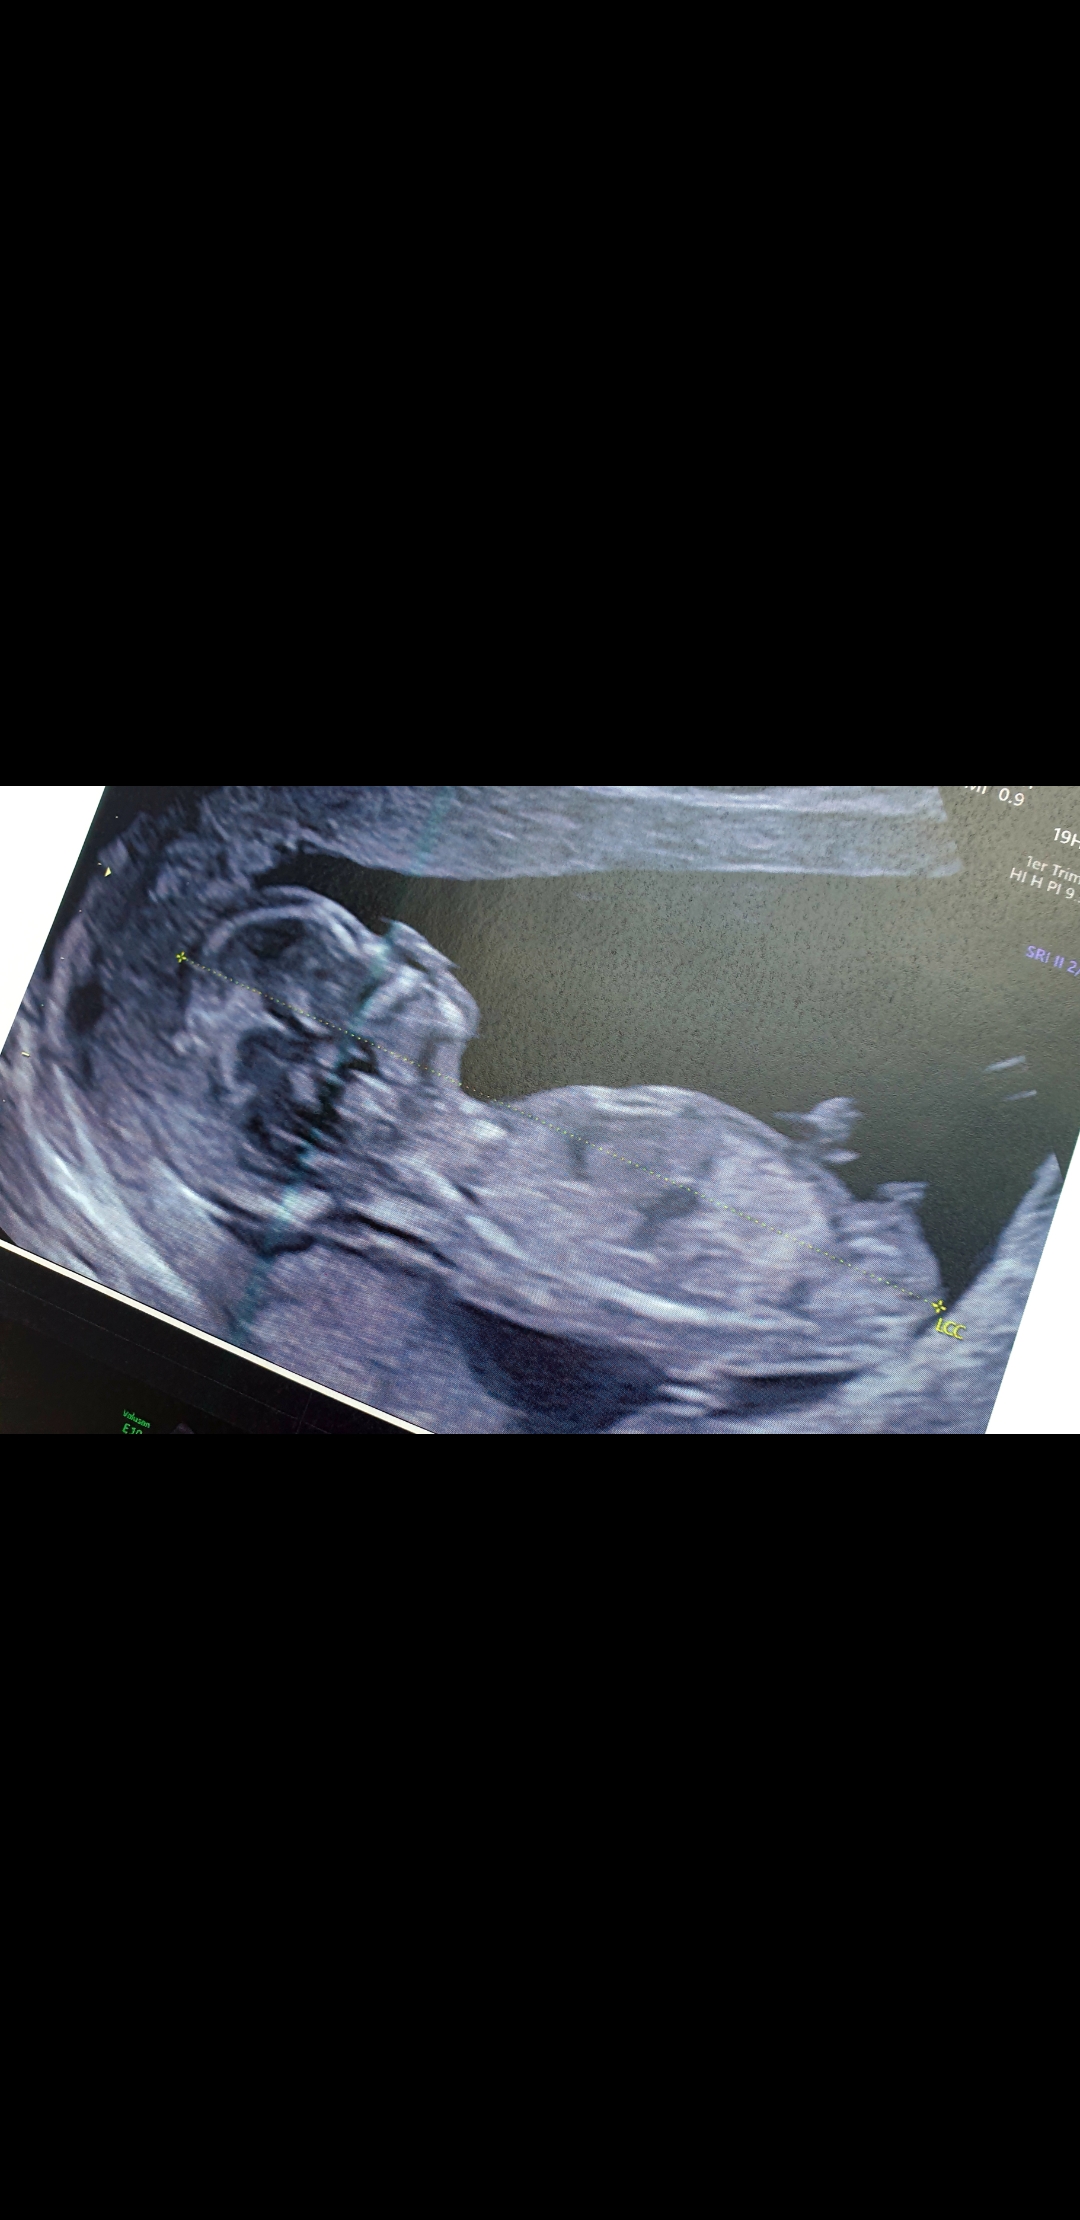

Savez vous si il existe un groupe ou les gens savent déchiffré les échographie faite du 1er trimestre pr le sexe

J’espère que tu va bien, je peut t’aider si tu veux il me faut le chiffre d la pulsation du ♡ du bébé